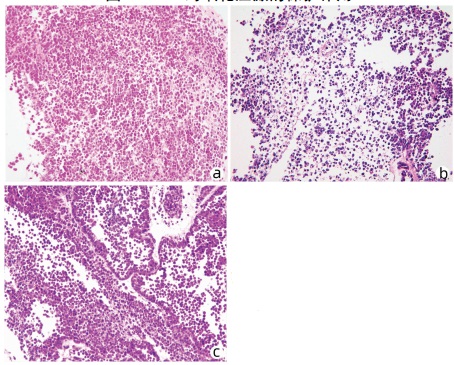

Lymphoepithelioma-like hepatocellular carcinoma: A case report

Xiaotong QIU, Zhengqi WU, Xuxiang XIA, Guoyue LYU

2022, 38(3): 634-635. DOI: 10.3969/j.issn.1001-5256.2022.03.027

Abstract(762) HTML (934) PDF (2924KB)(68)

Abstract: